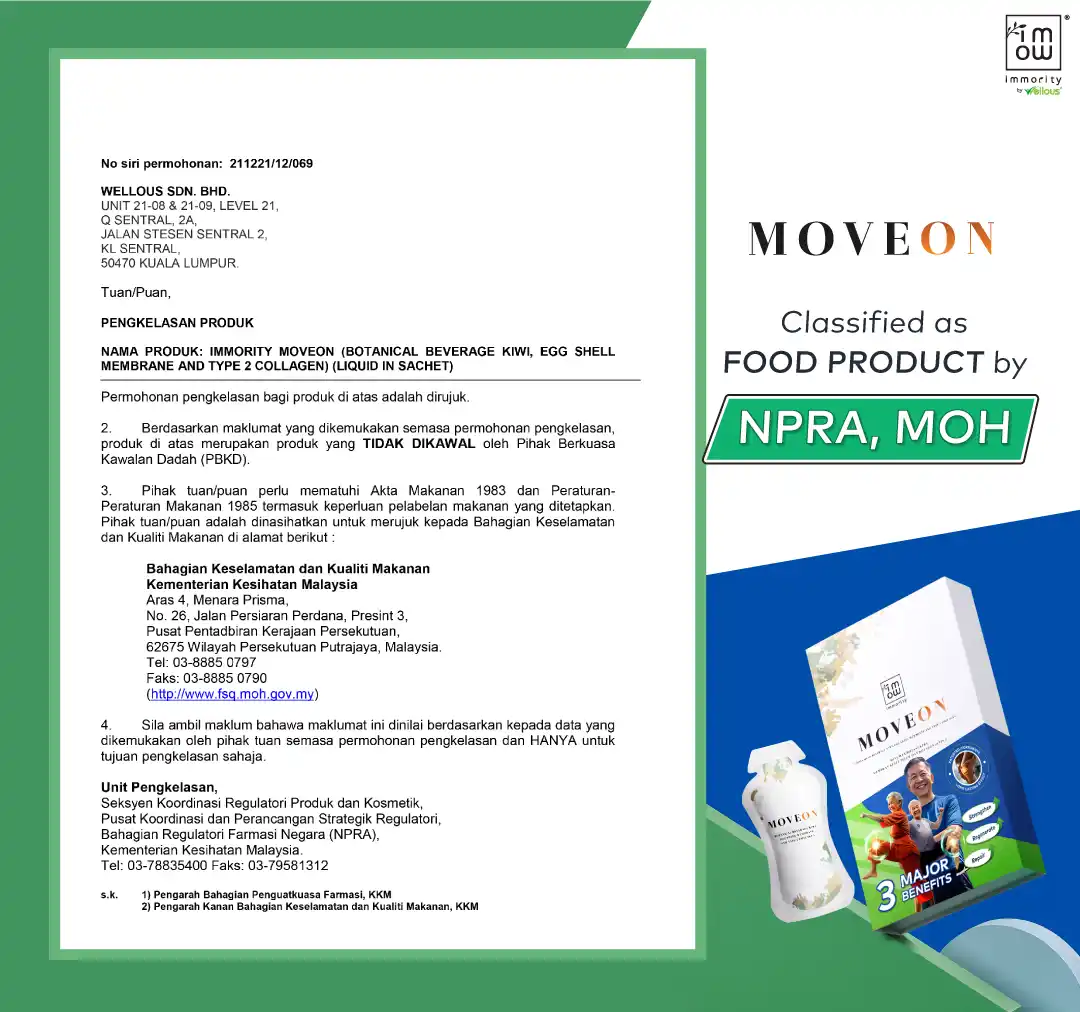

Approved by HSA& SFA, Trusted by 50,000 Singaporeans

100% Safe & Natural. 33 Years Of R&D, Approved by HSA, SFA, SGS, MOH & HALAL certified.

- Certified HALAL, HSA, SFA, USA FDA

Moveon Liveon is made from 100% natural ingredients, free from steroids, chemicals, or side effects. They are certified by HSA, SFA, HALAL, and USA FDA, and are safe for long-term use with no known side effects.